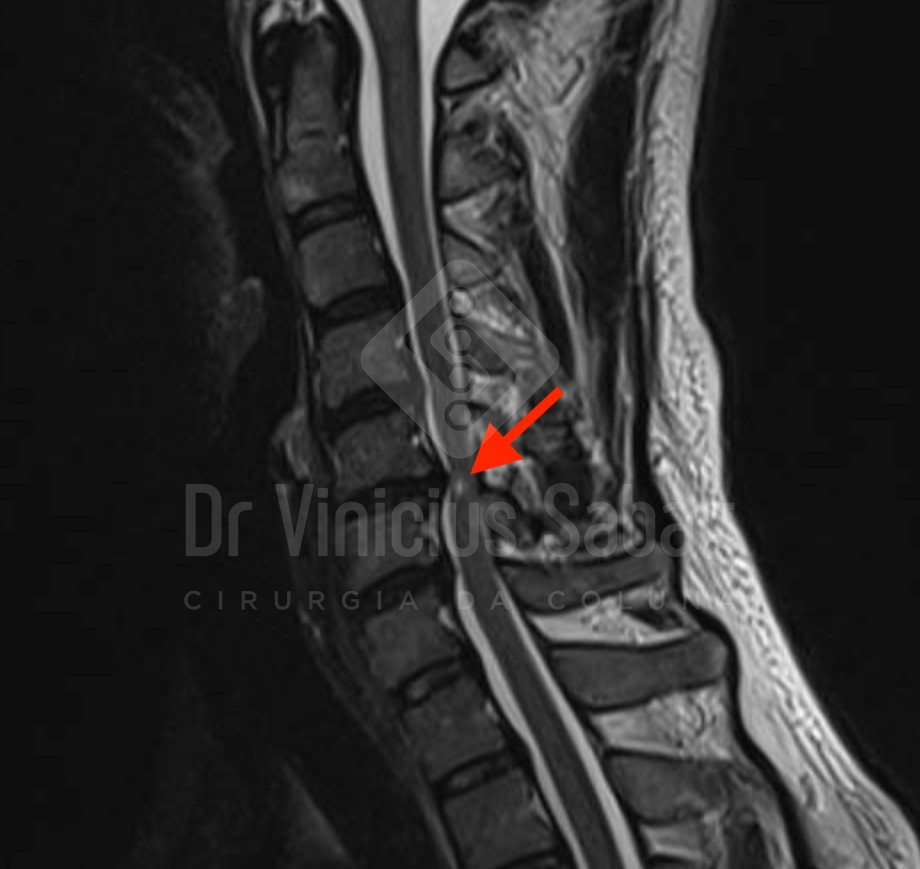

A ressonância magnética da coluna cervical evidenciou compressão significativa da medula espinhal, compatível com o diagnóstico de mielopatia cervical.

Ressonância magnética da coluna cervical evidenciando compressão medular grave. A área destacada em branco (seta) indica mielopatia cervical, sinal de sofrimento da medula espinhal.